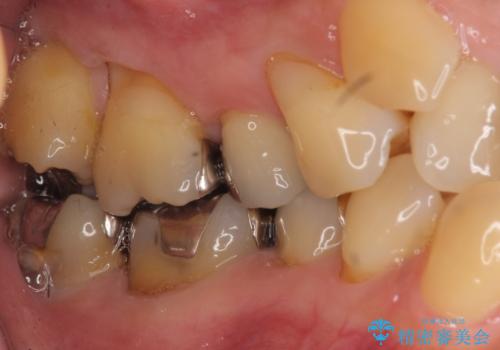

歯は入りきらないため、通常の抜歯矯正を行いました。

歯がご年齢的に動きにくいため、被せ物のやり替えを含めて治療期間の短縮を図りました。

詰め物や被せ物のやり替えも併せて行っているため、治療期間を比較的短縮できました。